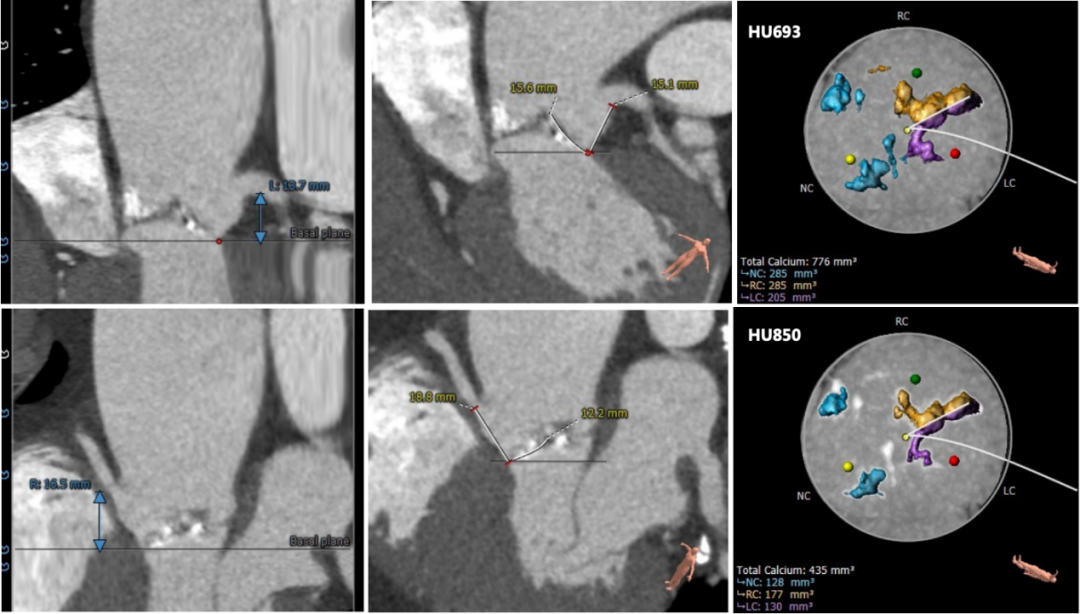

术前CT评估:

三叶式主动脉瓣,中度钙化并增厚,钙化分布不均匀,左右交界处存在似嵴样钙化。

左右冠高度尚可,左冠瓣瓣叶长度偏长,综合瓦氏窦内径等因素考虑,冠脉遮挡风险小。

左室流出道内径与瓣环内径相近,瓦氏窦,窦管交界内径可,升主动脉最宽处内径50mm,升主动脉瘤诊断明确。

主动脉瓣环与水平面夹角可,非横位心,主动脉弓降部角度较锐利,弓部宽度尚可。

主动脉根部测量

瓣上结构测量

冠脉阻挡风险及钙化评估